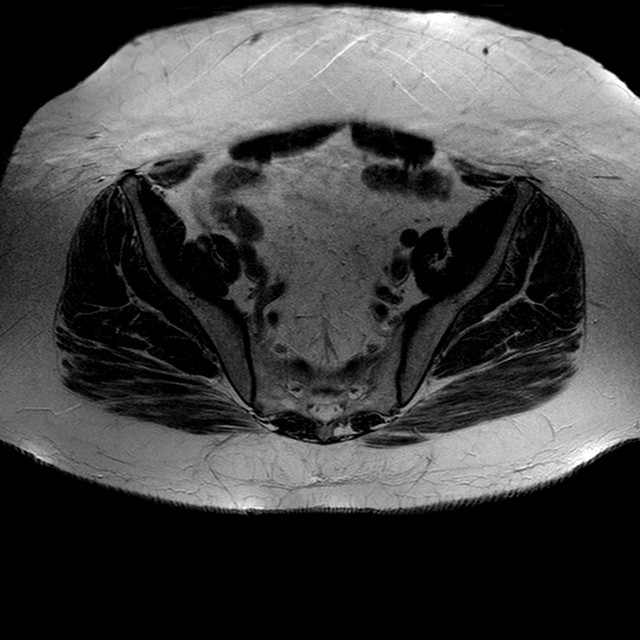

Esami: RMN BACINO

T2w TSE

Evidenti e simmetriche alterazioni osteofitosiche in regione coxo femorale con riduzione delle rime articolari. Degenerazione completa del cercine glenoideo. Non attuali segni di versamento articolare. Non segni di edema osseo che escludono attuale algodistrofia od osteonecrosi. Lieve e simmetrica riduzione del trofismo della muscolatura glutea.